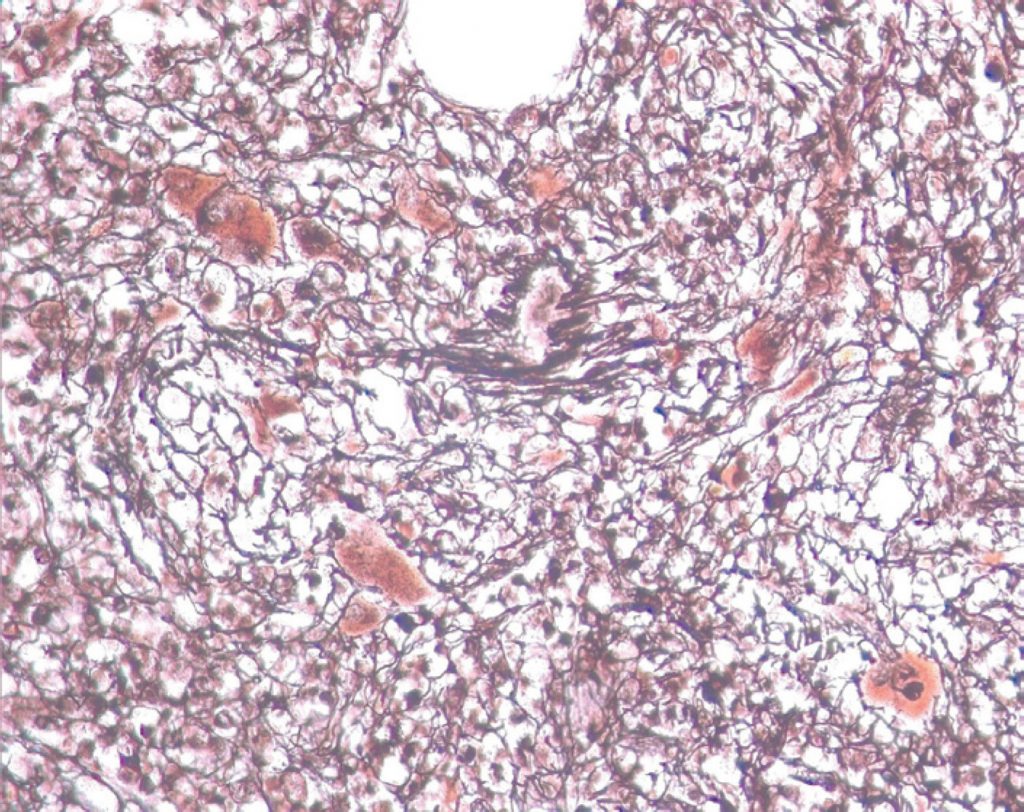

Mielofibrose acentuada, evidenciada por coloração específica (impregnação pela prata), mostrando megariócitos distorcidos de permeio a traves espessadas de reticulina